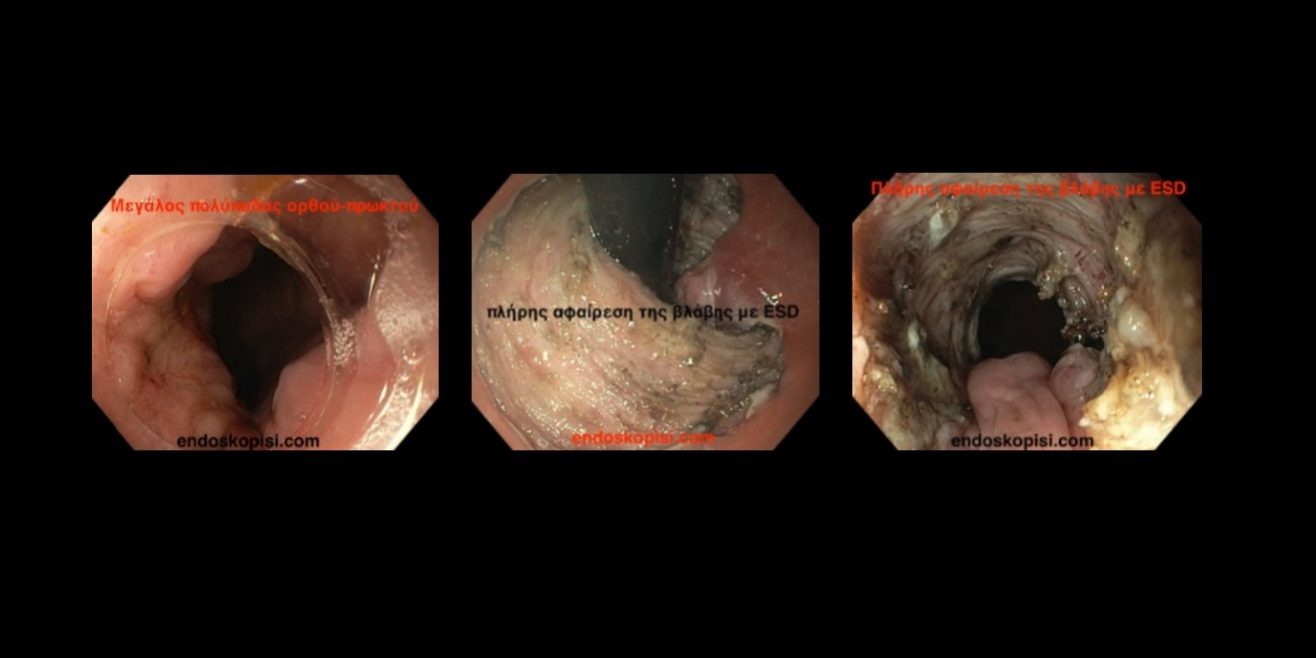

Πραγματοποιήθηκε επιτυχώς εκτομή πρώιμου καρκίνου ορθού και πρωκτού με την μέθοδο ESD. Ο κακοήθης πολύποδας επεκτεινόταν τόσο στον πρωκτό όσο και σε μεγάλη επιφάνεια του ορθού. Έγινε πλήρης αφαίρεση της βλάβης με την τεχνική ESD. Η ιστολογική ανάλυση έδειξε εστιακή κακοήθεια με υγιή όρια εκτομής. Η ασθενής απέφυγε την κολοστομία και επανήλθε άμεσα στην καθημερινότητά της.